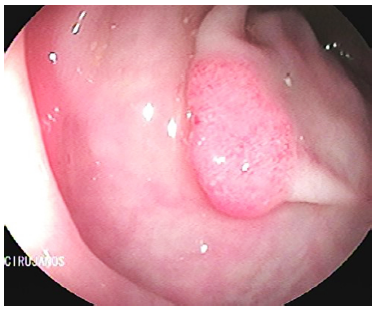

Se trata de una mujer de 58 años de edad quien consultó por un cuadro de pérdida anormal de peso de 6 kg en el último semestre, asociado con hematoquecia escasa y deposiciones diarreicas ocasionales, sin antecedentes patológicos, con antecedente familiar de cáncer de colon (hermana durante la quinta década de la vida). Se realizó una colonoscopia total que demostró tres pólipos: uno en el colon ascendente de 7 mm (biopsia: adenoma velloso con displasia de bajo grado) (Figura 1), un pólipo sésil de 50 mm en ángulo hepático (biopsia: adenoma velloso con displasia de bajo grado) (Figura 2) y un pólipo de 30 mm en el recto superior (biopsia: adenoma con displasia de bajo grado) (Figura 3); el hemograma resultó normal en las 3 líneas celulares. Se llevó a polipectomía endoscópica de pólipo rectal tipo piece meal con asa caliente, cuyo estudio histopatológico reportó adenoma tubulovelloso con displasia de bajo grado.